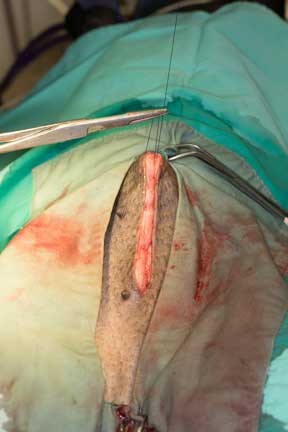

Special sutures are used to tie off the ovary before removal

More than one suture is used, and once Dr. R feels that the sutures are secure, he cuts out the ovary. The same thing is done with the ovary on the other side.

The body of the uterus is removed next. You can see it as that horizontal tube towards the left.